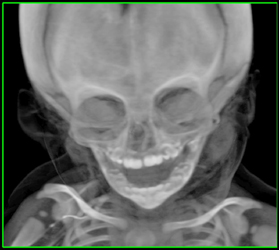

161

Normal Sutures

964